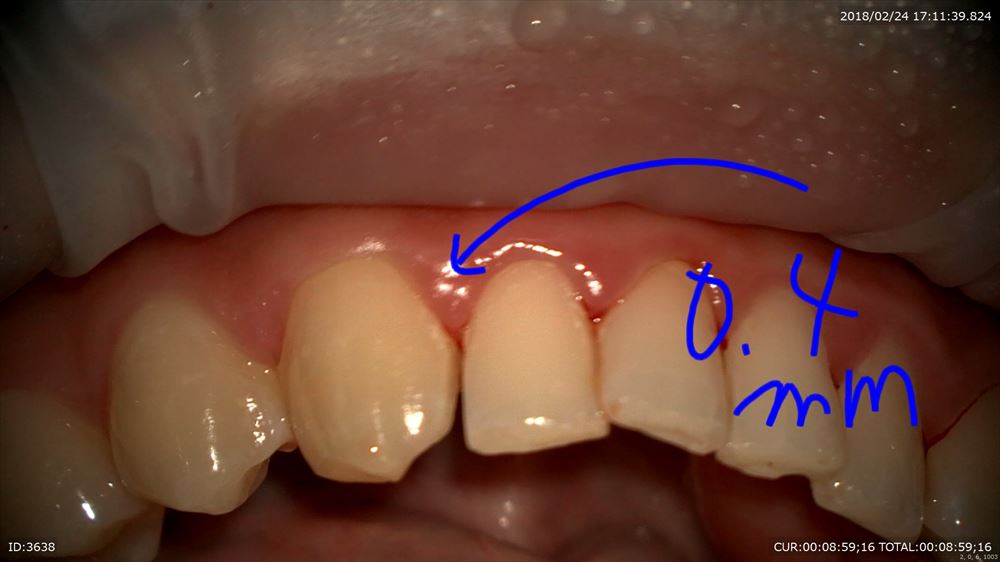

今回は0.4mmの研磨が必要となりました。

マイクロスコープを使用し研磨